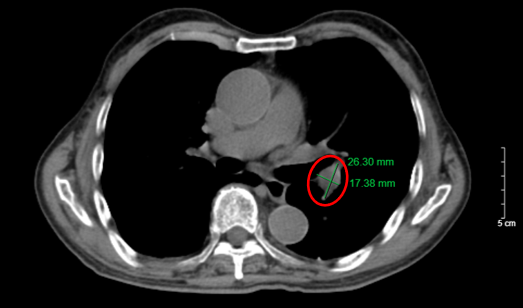

Hình 1. Hình ảnh nhu mô thùy trên phổi có nốt bờ không đều, tua gai, đường kính 26x17 mm (vòng tròn đỏ) trên phim chụp cắt lớp vi tính (cửa sổ trung thất).

Hình 2. Hình ảnh khối u bờ tua gai, đường kính 26x17 mm (vòng tròn đỏ), kèm hình ảnh dày tổ chức kẽ kèm các dải xẹp phổi nhu mô phổi trái. Giãn phế nang trung tâm lan tỏa rải rác nhu mô phổi, trên phim chụp cắt lớp vi tính (cửa sổ nhu mô).